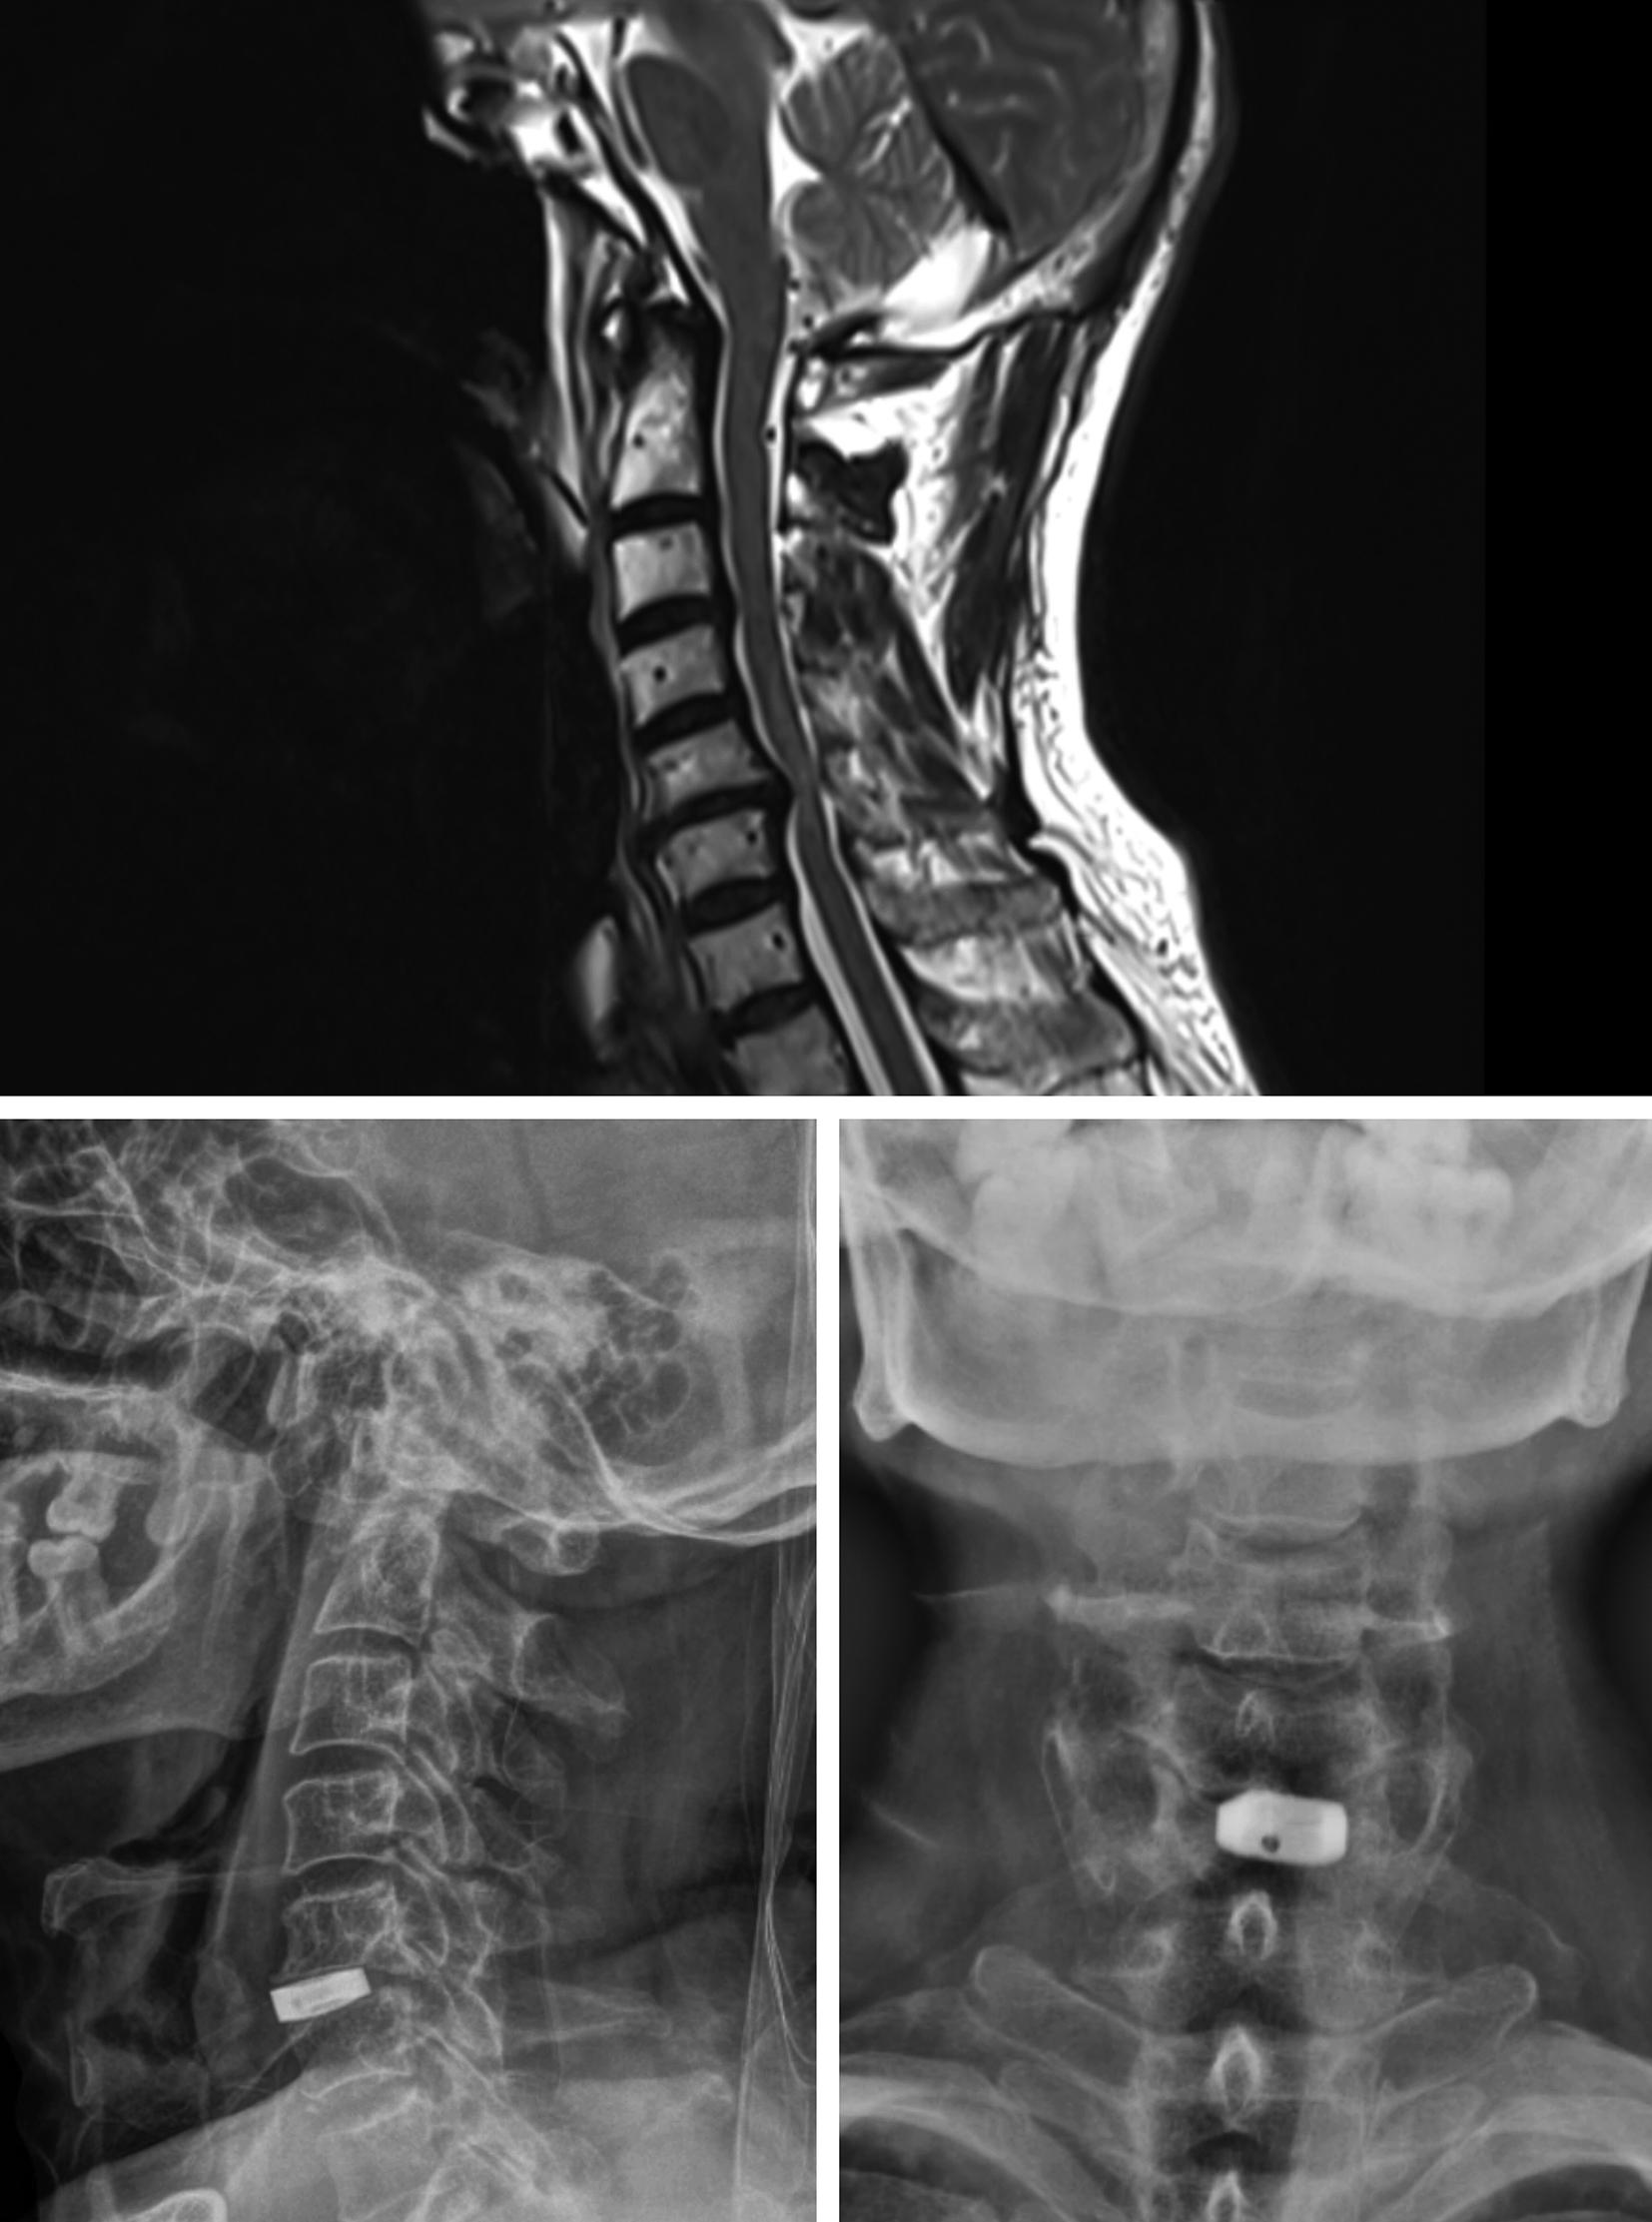

Figures 1-4 show pre-operative and post-operative radiological images in few of our patients.

Figure 3. A - Preoperative magnetic resonance imaging study of the cervical spine (T2 weighted image, sagittal view) showing cervical compressive myelopathy with disc osteophyte complex; B - Postoperative radiographic imaging study of the cervical spine (sagittal view) showing the cage in situ; C - Postoperative radiographic imaging study of the cervical spine (coronal view) showing the cage in situ